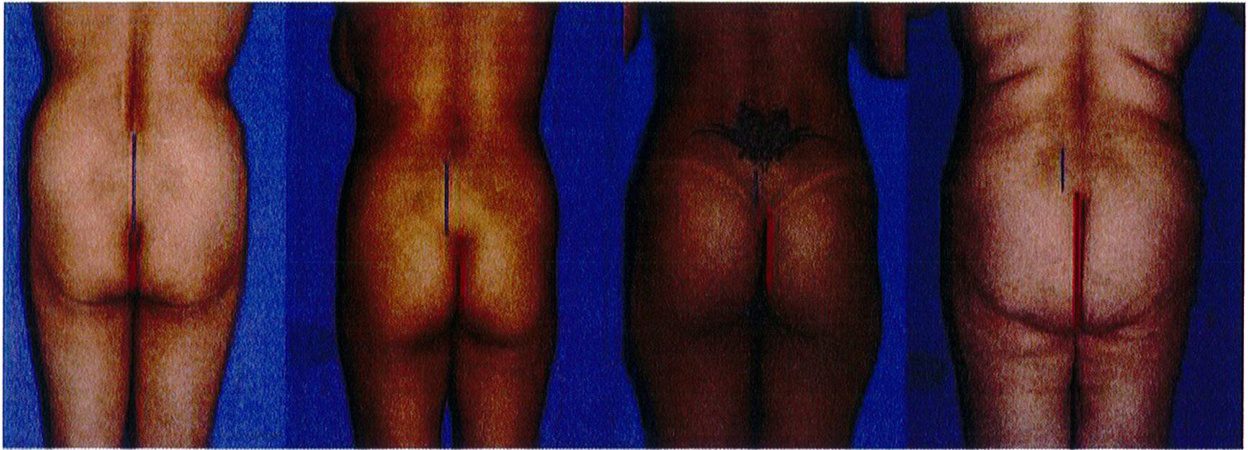

Hãy tưởng tượng bạn đang đặt khối cơ mông ở trên tay. Khi nhìn khối cơ từ phía sau (PA), vẽ một đường tưởng tượng thẳng xuống từ giữa khối cơ (Hình 17).

Xác định điểm trên cùng và dưới cùng của khối cơ Cũng như điểm sát cùng bên trong và bên ngoài. Từ đó xác định mối tương quan giữa chiều cao và chiều rộng (tỉ số cao/rộng). Thông thường chúng sẽ được chia thành 3 nhóm là ngắn/ thấp (tỉ số 1:1), cao (tỉ số 2:1) và trung gian (nằm giữa 2 tỉ số trên) (Xem hình 7 và 8). Một cơ mông lớn ‘lý tưởng’ sẽ thuộc nhóm trung gian, nhưng thường nghiêng về nhóm cao (2:1) (Xem hình 1A).

sẽ kêt luận đây là cơ mông có chiêu rộng hẹp. Nếu nó đi qua đường giữa mông này khoảng 10-30% thì được quy về chiều rộng bình thường. Và nếu vượt trên khoảng 40-50% thì được gọi là rộng. Mông đạt tiêu chuẩn thẩm mỹ ở người trẻ thuộc nhóm chiều rộng bình thường, và nếp lăn mông bên dưới chạy đến đường giữa hoặc chỉ vượt qua đường giữa mông đó 1 đoạn ngắn (Hình 1A).

Để xác định chiều rộng của khối cơ, vẽ 1 đường thẳng ở giữa mông (song song với đường liên mông). Sau đó xác định chiều rộng của nền khối cơ mông lớn từ đường giữa của cơ thể. Nếu đường đo nền khối cơ này (như hình 13, ảnh thứ 2 từ trái sang) không vượt quá đường thẳng vừa vẽ, chúng ta

Narrow base (50% line) Normal base Wide base (10-30% beyond central line) (40-50% beyond central line)

Hình. 17. Cách xác định chiều rộng phần nền khối cơ mông: hẹp, trung bình/ bình thường, hoặc rộng.

Narrow base(50% line : Hẹp (50% đường giữa) Normal base(10-30% beyond central line): Trung bình (vượt đường giữa 10- 30%) Wide base (40-50% bevond central line): Rôna (vươt đường aiữg 40-50% )